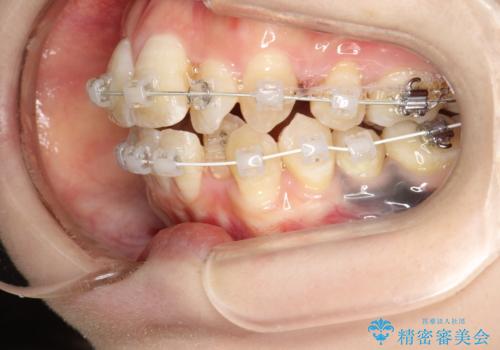

重度のガタガタ ワイヤーによる抜歯矯正

審美装置を用いた、抜歯矯正を行うこととしました。

抜歯したスペースを使うことで、ガタガタと出っ歯を改善することができました。